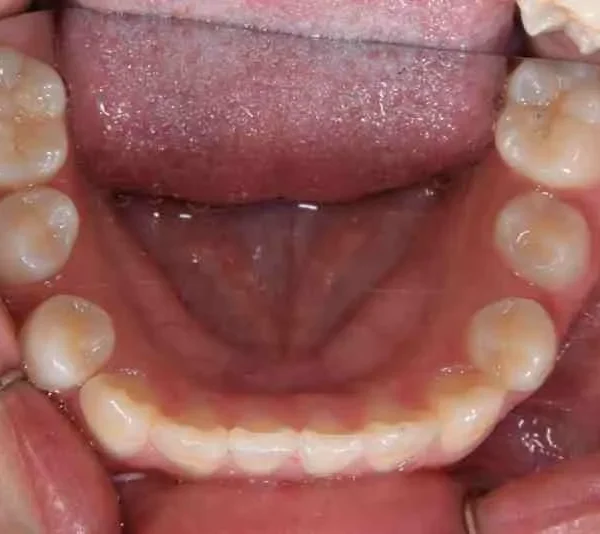

【子供の矯正(一期)】叢生・埋伏歯・受け口・永久歯が生える隙間がない・非抜歯症例・9歳女子【K.T様】

初診時年齢 小学校2年生 (女性) 主訴 受け口・がたがた

診断名 埋伏歯・反対咬合・叢生 装置名

拡大床

特徴 ゆがんで生えている

上の歯と下の歯で舌をはさむ癖がある

状態 永久歯が生える隙間がない(叢生)

受け口(下顎前突/反対咬合)

歯が埋まっている/歯がない(埋伏歯)

受け口で、ガタガタが有りました。

初診